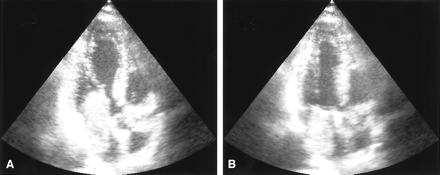

A 31-year-old man was admitted to our hospital with acute onset of dizziness, nausea, blurred vision of his left eye, and gait disturbance. On physical examination, he showed postural imbalance with tendency to fall to the right, dysarthria, skew deviation with a lower left bulb, and mild left-sided facial weakness. On cardiac examination, he had a regular rate and rhythm. No murmurs, rubs, or gallops were audible on auscultation. Duplex sonography gave normal results for his carotid, basilar, and vertebral arteries. Electrocardiography demonstrated signs of left atrial enlargement; a chest radiograph was normal. Holter electrocardiogram showed few ventricular and supraventricular extrasystoles but was otherwise regular. CSF results were normal, with no signs of hemorrhage or cytological abnormalities. Erythrocyte sedimentation rate was 30 mm after 1 hour. A preoperatively performed Coombs test was positive, with detection of cold agglutinins (anti-P1 antibody). All other laboratory results were normal. Cerebral MR imaging revealed multiple cerebellar and brain stem infarctions (Fig 1A, -B) as well as some smaller bihemispheric subcortical white matter lesions on T2-weighted images (not shown). There were no signs of intracranial bleeding. Gadolinium-enhanced T1-weighted sequences showed multiple small enhancing lesions probably corresponding to dilated blood vessels (Fig 1C, -D). Subsequent transthoracic and transesophageal echocardiography demonstrated a large mass with a suspected size of 2.5 × 2.5 × 7 cm in the left atrium, which prolapsed through the mitral valve into the left ventricle, suggesting the diagnosis of atrial myxoma (Fig 2). Cerebral angiography showed multiple intracranial microaneurysms up to 6 mm in diameter mainly localized in peripheral branches of middle, anterior, and posterior cerebral arteries; a few aneurysms were seen in branches of the vertebrobasilar arteries (Fig 3). One week after the initial neurologic event, fundoscopy was normal. A retinal fluorescein angiography revealed parafoveal teleangiectasias and microaneurysms in both eyes (Fig 4). Open heart surgery was performed, entirely removing the gelatinous tumor. Histologic examination confirmed the diagnosis of myxoma. After surgery, the patient was discharged from hospital without any specific treatment and recovered completely. Cerebral MR imaging 2 weeks after the operation showed the residues of cerebral infarctions and the cerebral aneurysm unchanged compared with the prior MR images. No new cerebral ischemic lesions were detected. Two years after the initial event, he was evaluated in the neurologic outpatient clinic and classified as being well, without any residual or newly developed symptoms.

Echocardiography demonstrating left atrial myxoma. Transesophageal echocardiogram in the two chamber view in diastole (A) and systole (B). A large intraatrial mass which prolapses through the mitral valve into the left ventricle in diastole (A) can be seen.